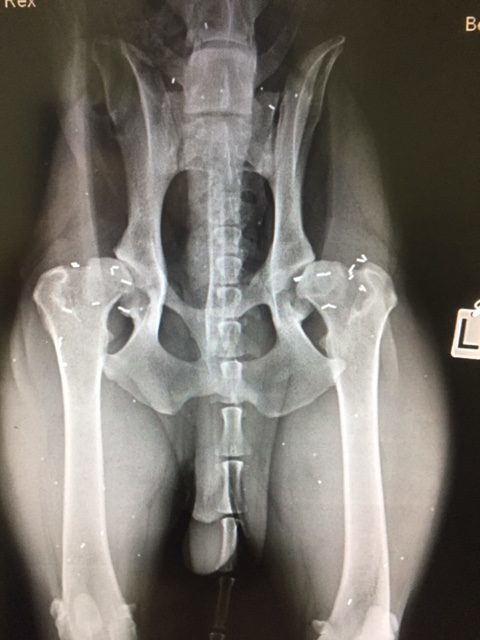

Fallbeispiel 1:  Rex, DSH-Rottweiler-Mix, 15 Monate alt

Rex hatte massive Probleme beim Aufstehen - und seine Hinterhandmuskulatur war wenig ausgeprägt. Er wurde mit neun Monaten in einer großen Klinik geröntgt. Dabei konnte eine schwere Hüftgelenksdysplasie (HD) festgestellt werden. Als Therapie wurde Abwarten vorgeschlagen. Später sollten dann zwei künstliche Hüftgelenke eingesetzt werden. Dem Hund ging es immer schlechter und wurde mir mit 15 Monaten vorgestellt. Die Triggerpunkte waren hochgradig schmerzhaft und in nur wenigen Monaten hatte sich beidseits eine starke Arthrose an den Hüftgelenken entwickelt. Die Goldakupunktur erfolge eine Woche nach der Erstvorstellung. Die Besitzer berichteten, dass Rex bereits zwei Tage nach dem Eingriff deutlich besser lief. Ihnen fiel auf, dass er jetzt in der Lage war, alleine auf die Couch zu springen, was er vorher nicht schaffte. Durch die Schmerzfreiheit konnte er sich viel aktiver bewegen, und die Muskulatur entwickelte sich im Laufe der nächsten Wochen hervorragend. Die Familie fuhr mit ihm an die Nordsee, wo er ohne Probleme mit anderen Hunden am Strand spielen konnte.